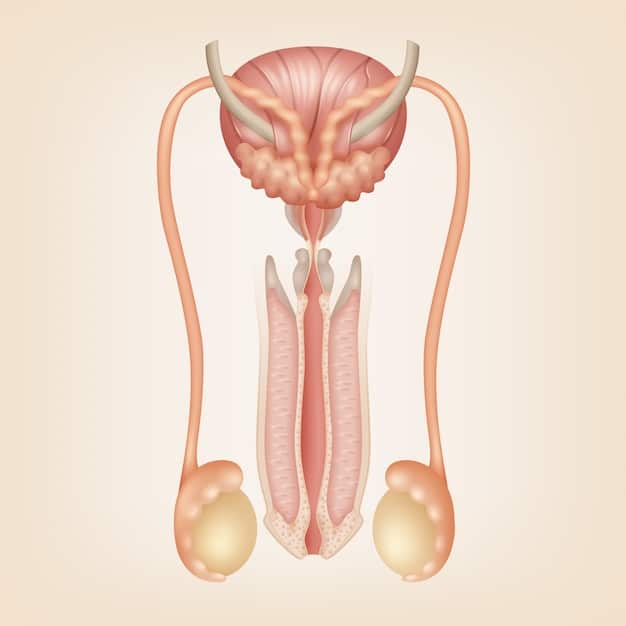

The external genitalia include the penis and the scrotum. The penis is the primary organ for sexual intercourse and urination, while the scrotum houses and protects the testicles.

The internal organs consist of the testicles, epididymis, vas deferens, seminal vesicles, prostate gland, and bulbourethral glands. Each organ plays a crucial role in sperm production, storage, and delivery.

- Testicles: Produce sperm and testosterone.

- Epididymis: Stores and matures sperm.

- Vas Deferens: Transports sperm from the epididymis to the ejaculatory ducts.

- Seminal Vesicles: Produce fluid that nourishes and protects sperm.

These organs work in harmony to facilitate reproductive function. Proper understanding of their roles is essential for maintaining sexual health.

In summary, the basics of male anatomy involve both external and internal organs, each with specific functions. Understanding these basics sets the stage for comprehending sexual function and potential health issues related to these organs.